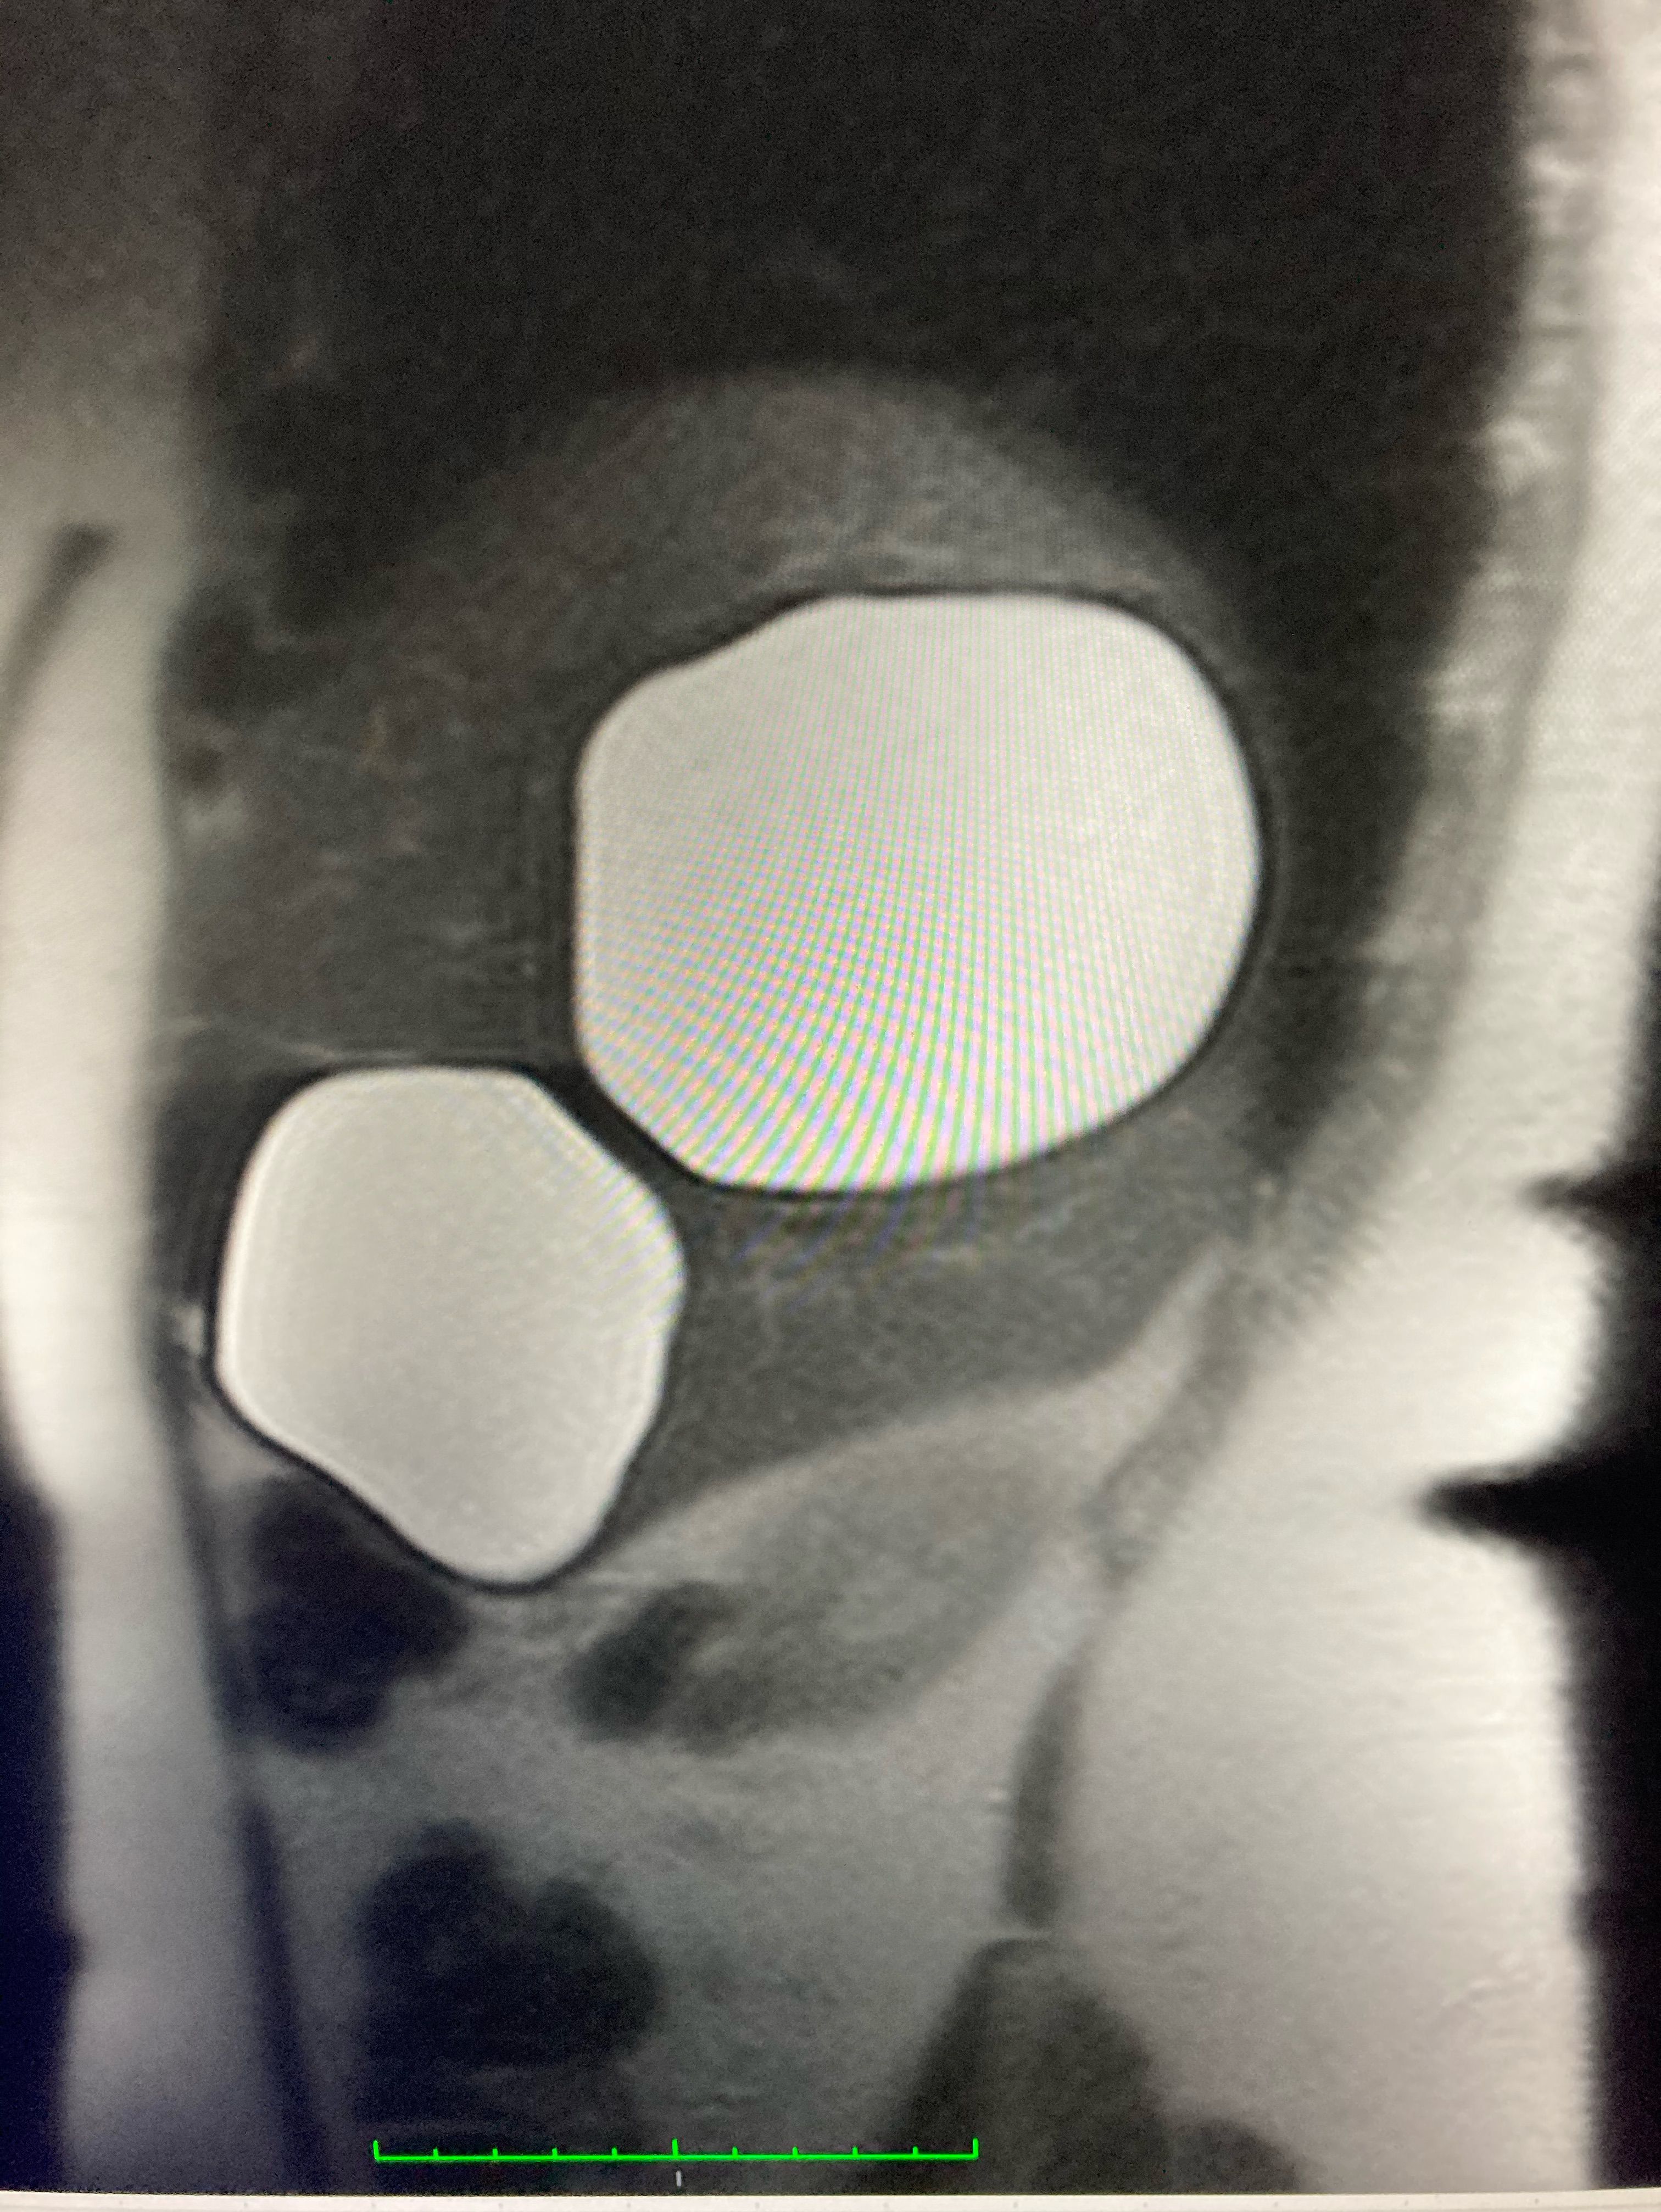

Echinococcal cysts of the liver. Preferred laparoscopic surgery.

Echinococcosis